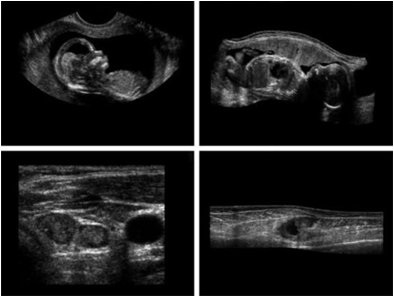

Other imaging modalities

- 지진 모델의 단면영상(화살표는 석유와 가스 트랲을 가리킴)

a)아기1 b)아기2 c)갑상선 d)손상된근육